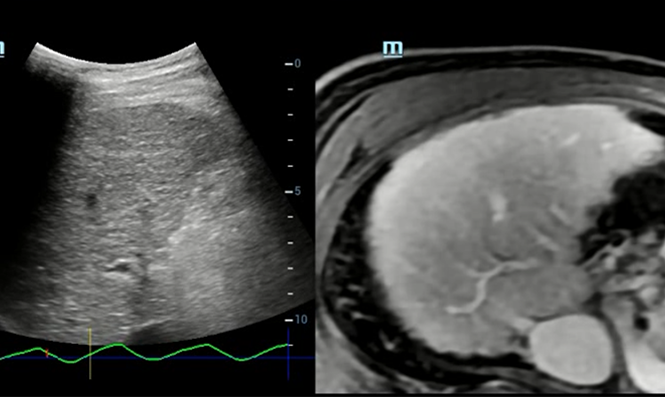

?valuation intelligente de la stûˋatose hûˋpatique par le calcul automatique de la luminositûˋ hûˋpatique avec le cortex rûˋnal en mode?B.

Imagerie de fusion ûˋchographique en 3D

Imagerie de fusion ûˋchographique en 3D

Compensation respiratoire

Compensation respiratoire